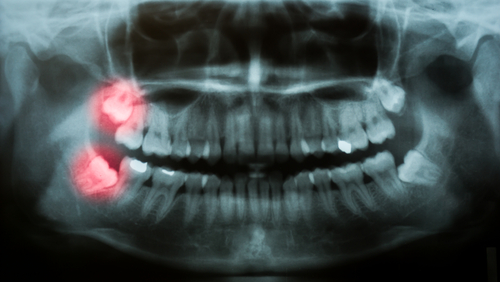

The top reason why most wisdom teeth need to be removed is that there’s simply not enough room in the mouth for these new teeth. Your dental x-rays will show your dentist whether or not there will be enough space for your wisdom teeth. However, if your mouth doesn’t have adequate room and you do not have your wisdom teeth removed, it can lead to overcrowding, crooked teeth, or even an impaction. Having impacted wisdom teeth essentially means that the teeth are stuck in your bone below the gum line. This can be very painful and increases the risk of infection.

Wisdom teeth also have a funny way of working themselves sideways and start to come through horizontally rather than vertically through the gums. If this occurs, nearby healthy teeth can be seriously damaged and your bite can be affected, causing larger, more serious, and painful problems.